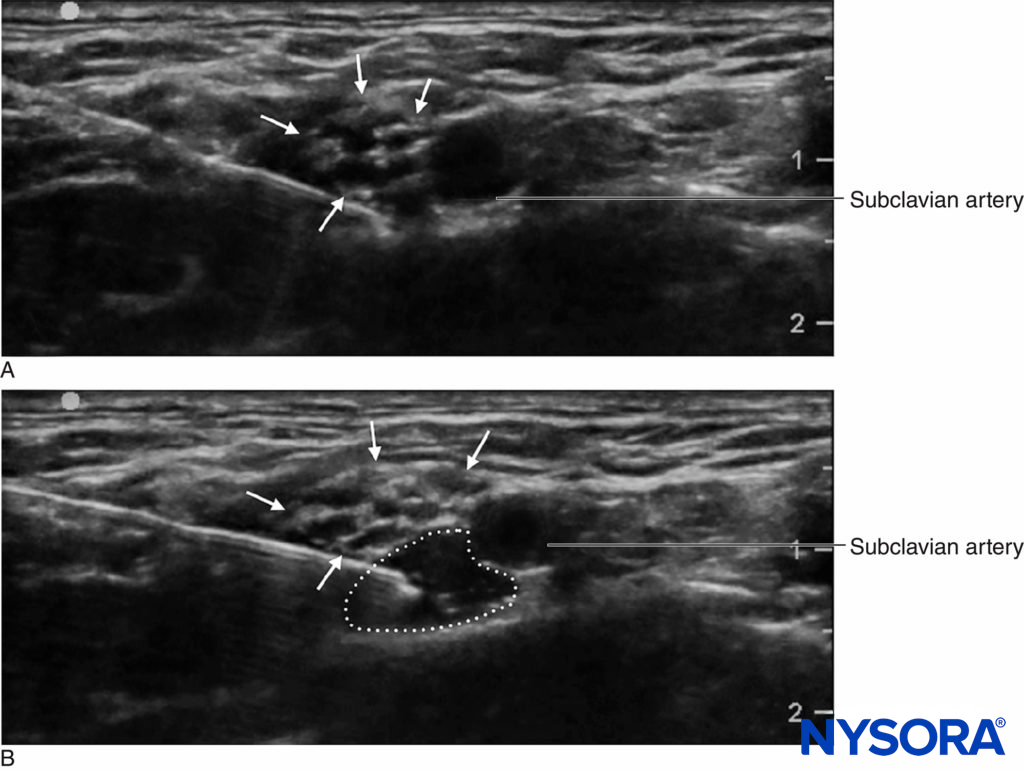

An important advantage of ultrasound screening is the ability to determine the distance from skin to target. This, coupled with needles that have depth markings etched on the side, confers an additional safety margin by warning the clinician of a “stop distance,” or a depth beyond which the clinician should stop advancing the needle to deeper tissue and reassess. Another important advantage that ultrasound is the ability to see the local anesthetic distribution in real time. (Figure 2). If corresponding tissue expansion is not seen when injection begins, then the needle tip may not be not where it is thought to be, and the clinician can halt injection and reassess the location of the needle tip. This is particularly important in vascular areas, as the lack of local anesthetic spread can signal intravascular needle placement. On the other hand, ultrasound monitoring can be used to diagnose intra-arterial needle-tip placement when an echogenic “blush” is noted in the lumen of the artery, decreasing the risk of systemic toxicity.

FIGURE 2. Supraclavicular brachial plexus block showing plexus (arrows) adjacent to subclavian artery (SA). A Before and B after deposition of 10 mL of local anesthetic (dotted outline).